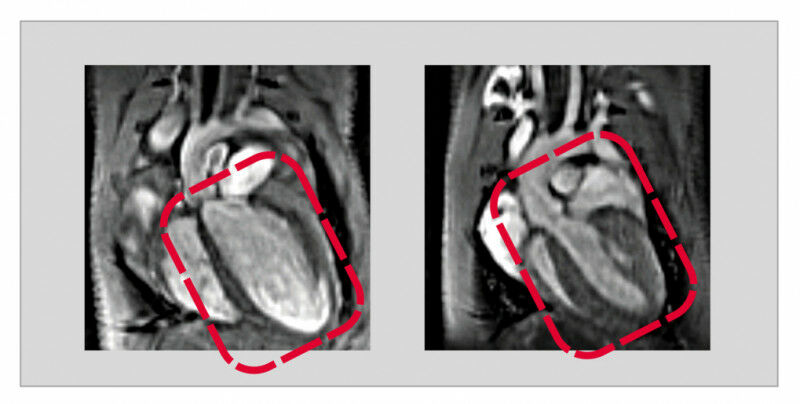

Die Bad Nauheimer Wissenschaftlerinnen stellten nun in Experimenten in Tierversuchen an Mäusen fest, dass niedrige USP5-Spiegel eine dilatative Kardiomyopathie auslösen. -Durch einen gentechnischen Eingriff konnten wir in den Herzmuskelzellen ausgewachsener Tiere USP5 gezielt ausschalten. Fehlte dann das USP5, entwickelte sich in der Folge eine dilatative Kardiomyopathie-, berichtet Silke Kreher. Co-Autorin Yvonne Eibach fügt hinzu: -Mit Hilfe der Magnetresonanztomografie als Bildgebungsverfahren konnten wir eindrucksvoll nachweisen, dass bei diesen Tieren das gesamte Herz deutlich vergrößert und die Pumpleistung stark eingeschränkt ist.- Unter dem Mikroskop stellten die Forscherinnen darüber hinaus vermehrt Proteinablagerungen fest, was eine direkte Folge des gestörten Abbaus von Proteinen ist, da diese ohne USP5 nicht mehr den Weg in die Proteasomen finden.